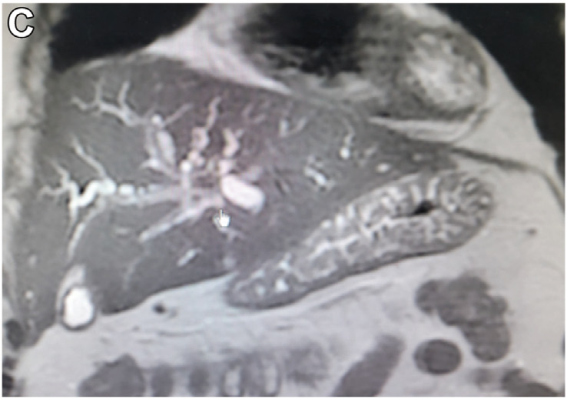

病史摘要:33岁女性患者,数月来右上腹间歇性不适,伴早饱、腹胀及恶心,症状反复后就诊。 诊疗过程:体格检查无明显异常。实验室检查肝功能及肿瘤标志物正常,尿妊娠试验阴性。腹盆部增强CT见肝内3个不明病灶;腹部MRI显示病灶有包膜皱缩、弥散受限等特征,出现“棒棒糖征”。主要诊断为肝上皮样血管内皮细胞瘤(EHE),鉴别排除转移瘤等疾病。经皮穿刺活检病理及免疫组化确诊EHE。随访8个月病灶大小